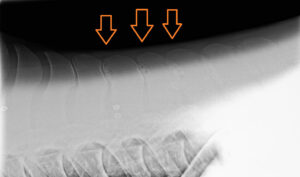

Once we have established that there is clinical primary back pain, radiographs are the gold standard to assess the underlying bone. Interpretation can, however, be complicated. There have been cases of kissing spines reported with minimal boney changes (such as sclerosis and lysis) on radiographs, while other cases have boney changes to the dorsal spinous processes with no clinical problem (Erichsen et. al. 2004). The back is also a mobile structure; with the distance between the dorsal spinous processes strongly affected by the way the horse is standing (Berner et. al. 2012). Depending on how the horse is standing, the space between the dorsal spinous processes can be appear very narrow when they are in fact normal. It is because of this difficulty in interpretation that we often combine radiographs with other modalities to confidently diagnose kissing spines.

Image above: Kissing spine radiography image